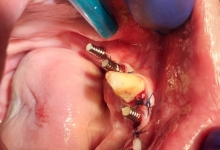

Boala parodontala are un caracter progresiv. Pentru cazurile mai grave, recomandam tratamentul parodontal chirurgical rezectiv sau regenerativ.

IMPLANTOLOGIE

SUPRAPROTEZAREA PE IMPLANT